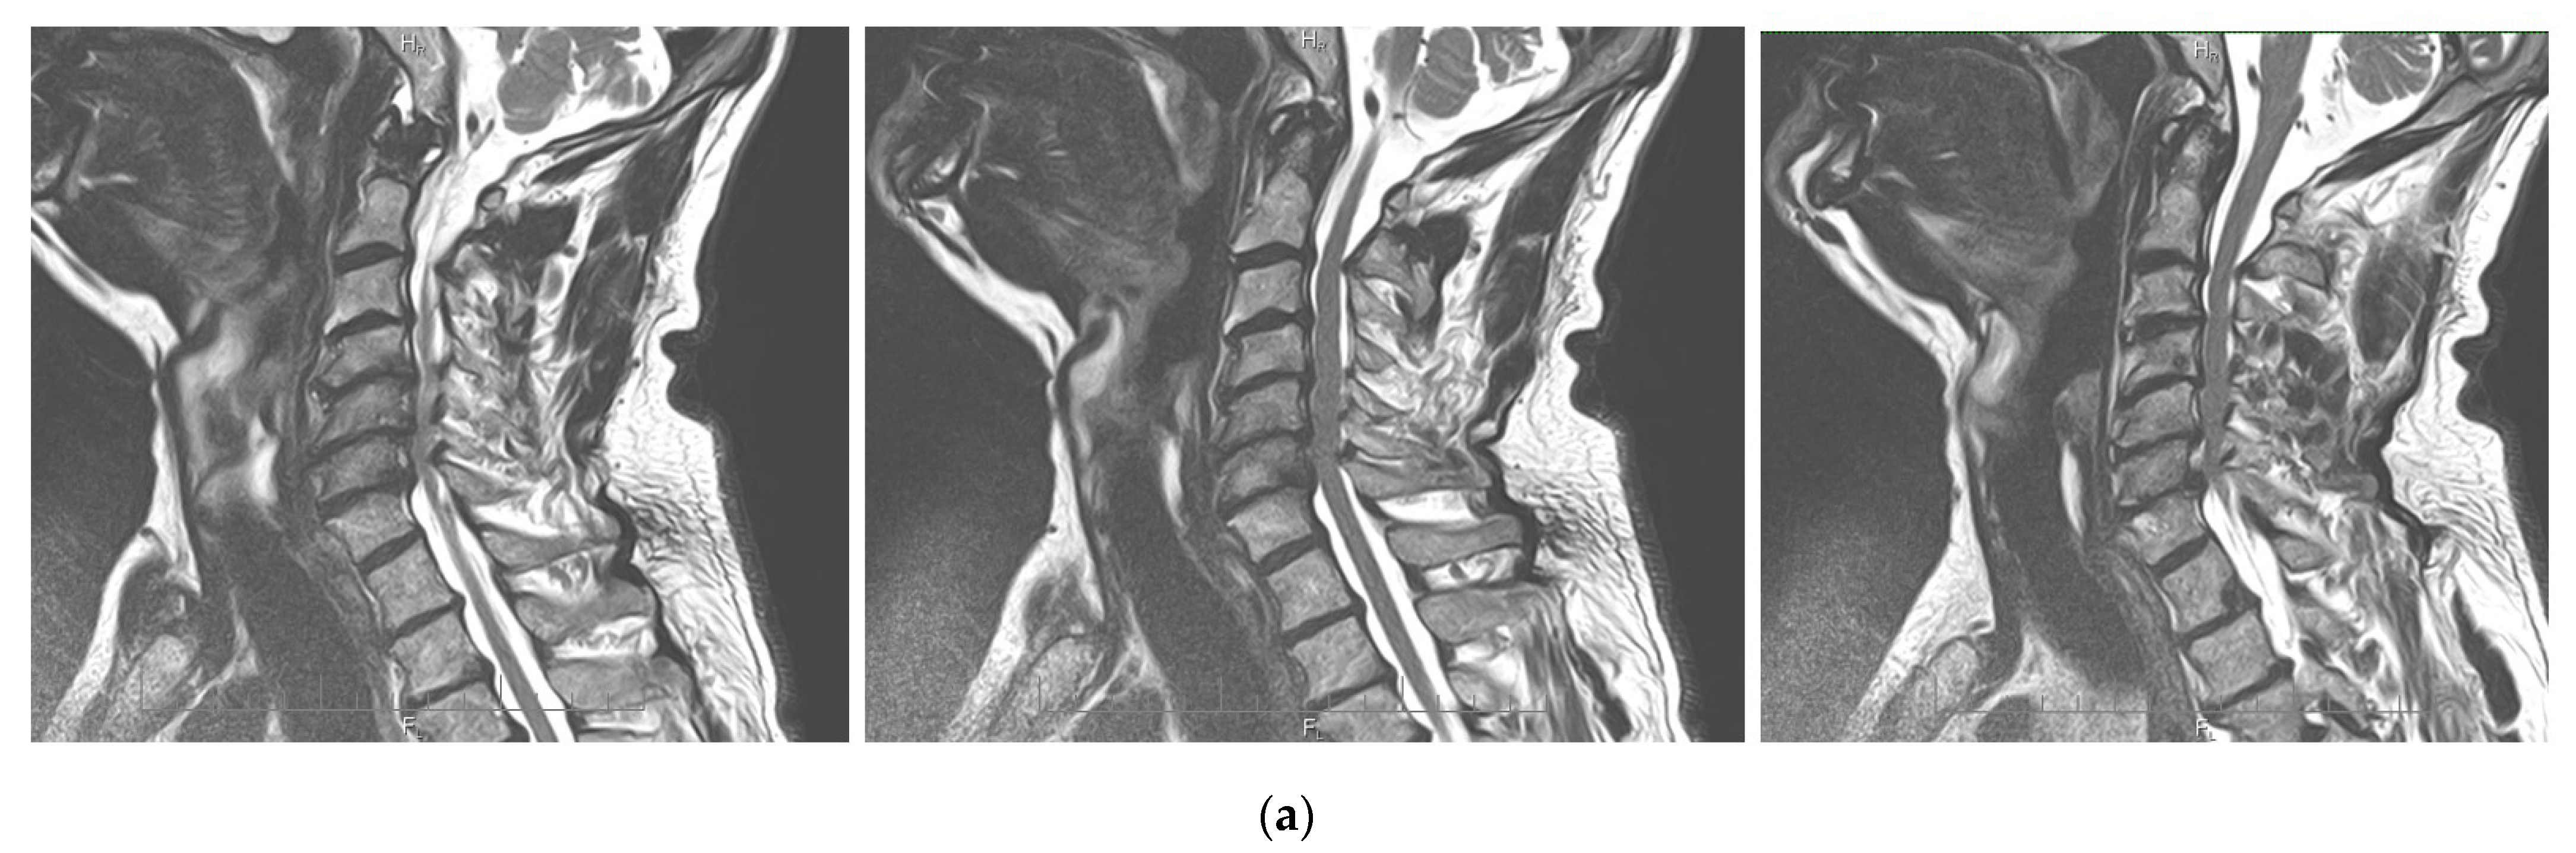

2.4. Neuroimaging